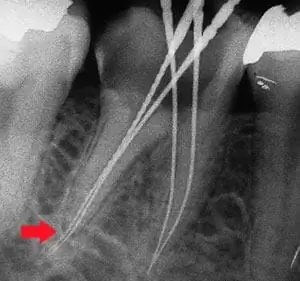

根管探測剉針刺穿根尖

有了顯微鏡輔助根管治療,較不會造成如圖示:根尖刺穿的情況發生。